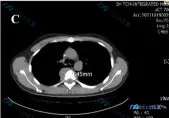

今天整理了一个很有警示意义的病例资料,核心线索是治疗前后CT对比发现T5椎体右侧软组织肿块增大至33.81mm,同时影像还附带发现了降主动脉的异常,整个分析过程差点走偏,分享一下思路。 --- 先把关键客观信息摆出来 1. 核心动态变化:治疗后随访,T5椎旁右侧软组织肿块较前增大,现大小约33.81...